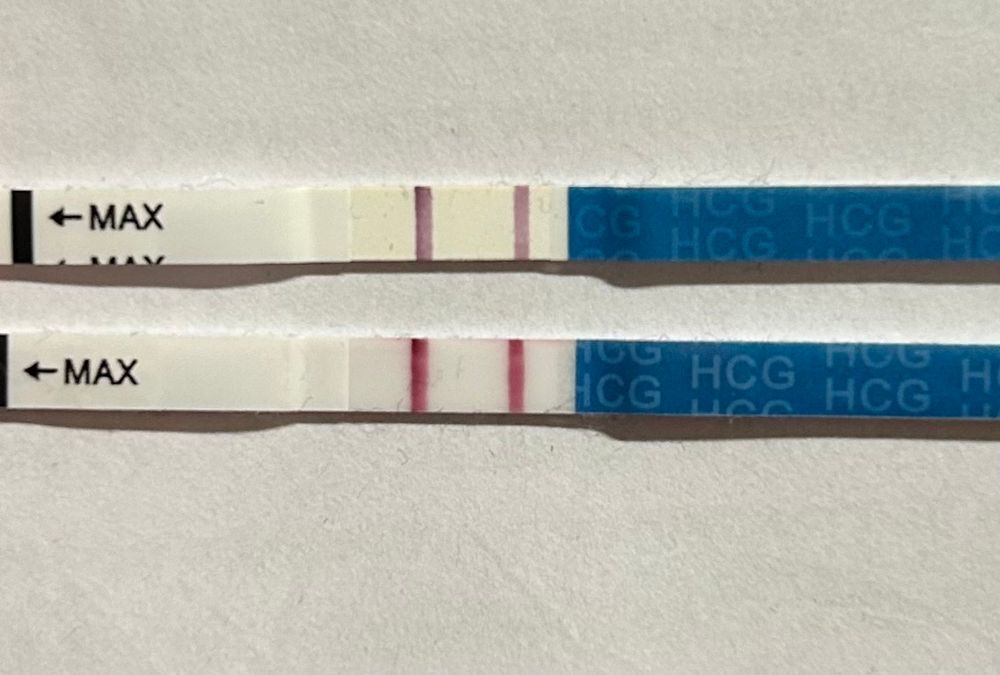

Хгч

Девочки, как думаете сколько примерно хгч при таких тестах ( тест МамаЧек) 🥰

Думаю около 1000)